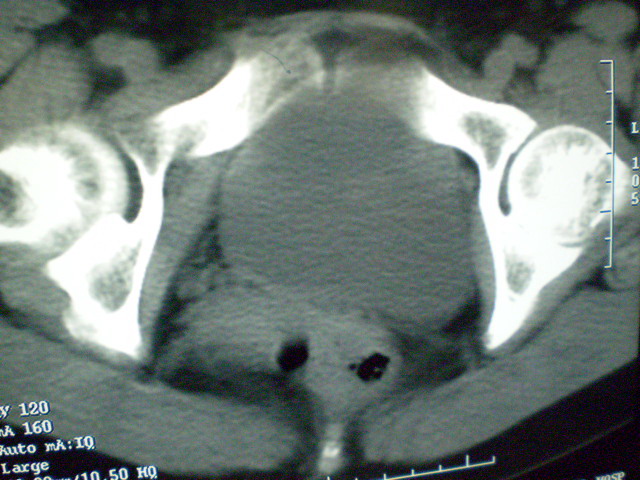

f 60y,b超提示脂肪瘤.[img][/img]

右侧附件囊性畸胎瘤,三种组织均见.

那个高密度灶形状好象牙齿。典型,收藏了

脂肪密度肿块,内可见团块状影,典型皮样囊肿

的确比较典型的畸胎瘤!不过,应该确切的说是盆腔畸胎瘤,右侧附件来源的可能性比较大。